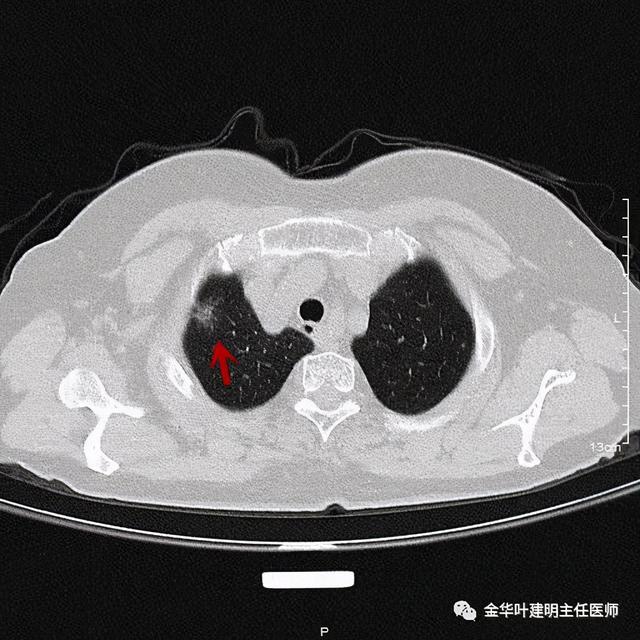

靶扫描更清楚显示瘤肺边界较清、分叶及密度不均杂乱 , 并有少许胸膜牵拉凹陷 , 当然考虑是肺癌 , 而且应该是浸润性腺癌了 。 其长径达2.5厘米!靶扫描还发现了平扫没被注意到的另一个病灶:

文章插图